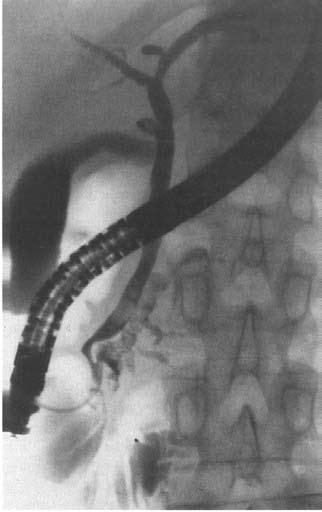

Ретроградная холангиопанкреатикография (РХПГ), позволяющая контрастировать вирсунгов проток, выполняется в ходе эндоскопического исследования (подробнее см. ниже) (рис. 132).

Рис. 132. Ретроградная панкреатикография при хроническом панкреатите. На снимке виден резко расширенный главный панкреатический проток

Рис. 133. Ретроградная холангиопанкреа‑тография. Контрастированы желчные протоки и желчный пузырь и главный панкреатический проток. Имеется продленное сужение (симптом «мышиного хвостика») терминального отдела общего желчного протока (панкреатическая часть) и резкое расширение главного панкреатического протока с нечеткостью его контуров

На рентгенограмме могут быть обнаружены характерные для ХП признаки: расширение главного панкреатического протока иногда в виде контрастной «цепи озер», наличие в протоке стриктур, конкрементов, а также сообщающихся с протоком полостей (псевдокист). На одновременно осуществляемой холангиограмме может выявляться стриктура терминальной части холедоха, расширение вне‑и внутрипеченочных желчных протоков, холедохолитиаз и т. д. Учитывая возможные осложнения РХПГ (острый панкреатит, острый холангит вплоть до развития бактериально‑септического шока при наличии инфекции в протоках до РХПГ), это исследование выполняется в основном по абсолютным показаниям, перед операцией или с одновременной эндоскопической декомпрессией протоков.